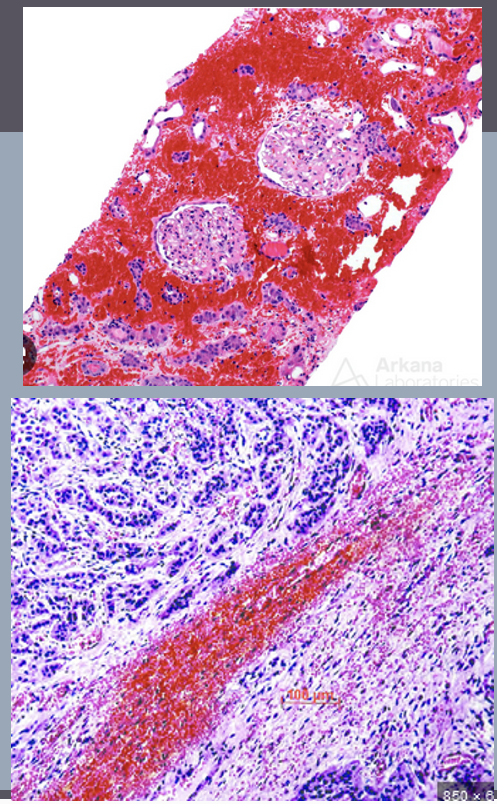

Brown color = presence of cytokeratin = epithelial tumor → carcinoma

Pathologists can often identify a tumor’s tissue of origin by examining how its cells are arranged, but some tumors are too poorly differentiated to determine this by appearance alone. Knowing the origin is important because it influences treatment choices (e.g., radiation for connective tissue tumors, chemotherapy for epithelial tumors). To help identify the tissue type, immunohistochemistry is used: antibodies tagged with peroxidase bind to specific intermediate filaments in the cells. When a substrate is added, peroxidase produces a brown color wherever binding occurs. For example, if cells stain brown with a cytokeratin antibody, the tumor is confirmed to be epithelial in origin, though further tests are needed for a more specific diagnosis.